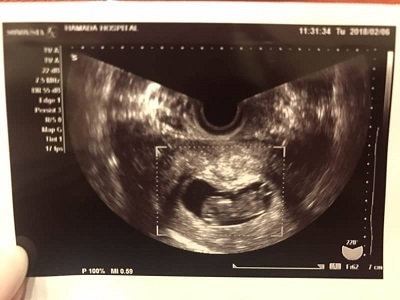

9週4日(9w4d・女の子)|llmitsui さん(36歳)

エコー写真撮影時のエピソード:つわりが現れ始めました。1日食欲がなく、吐きたくなる回数が増えました。電車に長時間乗ってしまう時に気分が悪くなるケースが多いです。

でもエコー写真を見てると、なんだか嬉しくて堪らないです。なぜか経腟超音波のほうが、お腹の上から撮影したものより、赤ちゃんっぽく見えてしまいます。